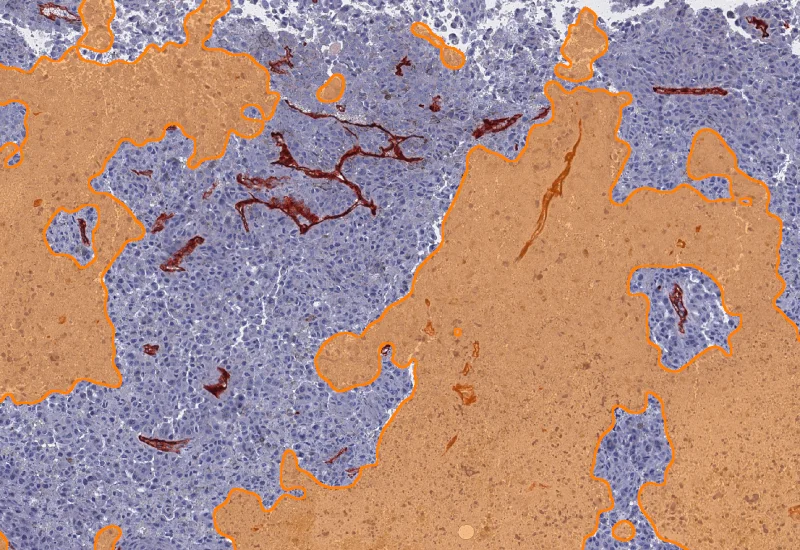

IHC Necrotic Tumor Angio

Segment tumor tissue into tumor, necrotic tissue, and blood vessels using an AI classifier, and quantify compartment areas, total vessel count, and vessel distribution across morphological entities.

The IHC Necrotic Tumor Angio App is able to segment tumor tissues into tumor, necrotic tissue and blood vessels using the AI Classifier. It outputs area of tumor, necrotic tissue and blood vessels as well as the number and percentage of blood vessels in total and within the two morphological entities.